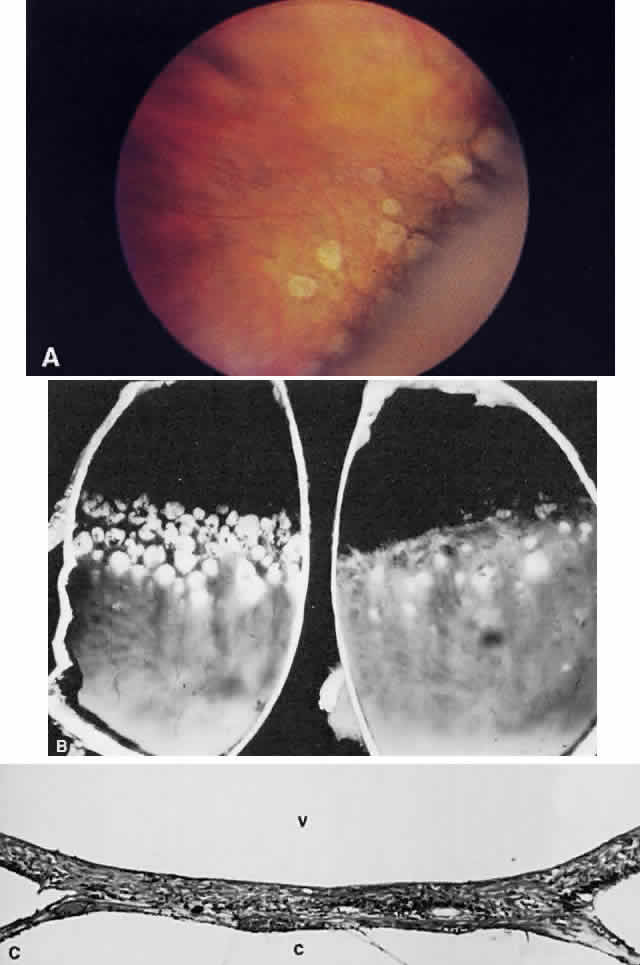

organization of intraocular hemorrhage.7 The white “snow bank” seen on the inferior pars plana and retinal

periphery in chronic pars planitis represents organization of inflammatory

protein and cells with contributions from glial cells as well

as fibroblasts (presumably derived from nonpigmented ciliary epithelium).8 Organization of old vitreous hemorrhage also may appear white for similar

myelinization does not halt abruptly (Fig. 21).  Fig. 21. Myelination of the nerve fibers extending beyond the disc. Notice the feathery

edges to the termination of the myelin. (Courtesy of William Tasman, MD, Philadelphia, PA) Fig. 21. Myelination of the nerve fibers extending beyond the disc. Notice the feathery

edges to the termination of the myelin. (Courtesy of William Tasman, MD, Philadelphia, PA)

cells and were called “cytoid [cell-like] bodies” (Fig. 22).  Fig. 22. Histologic section demonstrating retinal nerve fiber layer infarct. The

red dots within the infarct zone are bulbous swellings of nerve fiber

axons called “cytoid (cell-like) bodies.” The entire infarcted

zone is the histologic counterpart of the clinical cotton-wool spot. (Courtesy of Ralph C. Eagle Jr, MD, Philadelphia, PA) Fig. 22. Histologic section demonstrating retinal nerve fiber layer infarct. The

red dots within the infarct zone are bulbous swellings of nerve fiber

axons called “cytoid (cell-like) bodies.” The entire infarcted

zone is the histologic counterpart of the clinical cotton-wool spot. (Courtesy of Ralph C. Eagle Jr, MD, Philadelphia, PA)

Cotton-wool spots are observed mainly in the posterior pole of the retina (Fig.23) The reason for this geographic restriction is not clear. Occlusion of

the most superficial radially oriented peripapillary capillaries (confined

in distribution to the posterior pole) has been implicated in the

pathogenesis of cotton-wool spots.9 It is also possible that nerve fiber infarcts in the periphery are not

visualized because there is insufficient inspissated axoplasmic material

in this location.  Fig. 23. Multiple cotton-wool spots along with retinal hemorrhages in a superior

temporal branch retinal vein occlusion. Fig. 23. Multiple cotton-wool spots along with retinal hemorrhages in a superior

temporal branch retinal vein occlusion.

|

membrane.  Fig. 28. Photomicrograph of drusen of the optic nerve head. Calcium (c) is deposited in the nerve anterior to the lamina scleralis. The optic

nerve in this case is markedly atrophic. The retina to the left of the

nerve is artifactually detached and missing from the plane of the section. Fig. 28. Photomicrograph of drusen of the optic nerve head. Calcium (c) is deposited in the nerve anterior to the lamina scleralis. The optic

nerve in this case is markedly atrophic. The retina to the left of the

nerve is artifactually detached and missing from the plane of the section.

Fig. 30. A. Photomicrograph of an optic disc with papilledema. There is edema of the

disc surface, some engorgement of the vessels, and lateral displacement

of the photoreceptor elements, which results in enlargement of the

blind spot in papilledema. B. Early papilledema in a patient with pseudotumor cerebri. The disc margin

is blurred, the surface slightly elevated, and a small hemorrhage is

present superiorly. (A, courtesy of Ralph C. Eagle Jr, MD, Philadelphia, PA) Fig. 30. A. Photomicrograph of an optic disc with papilledema. There is edema of the

disc surface, some engorgement of the vessels, and lateral displacement

of the photoreceptor elements, which results in enlargement of the

blind spot in papilledema. B. Early papilledema in a patient with pseudotumor cerebri. The disc margin

is blurred, the surface slightly elevated, and a small hemorrhage is

present superiorly. (A, courtesy of Ralph C. Eagle Jr, MD, Philadelphia, PA)